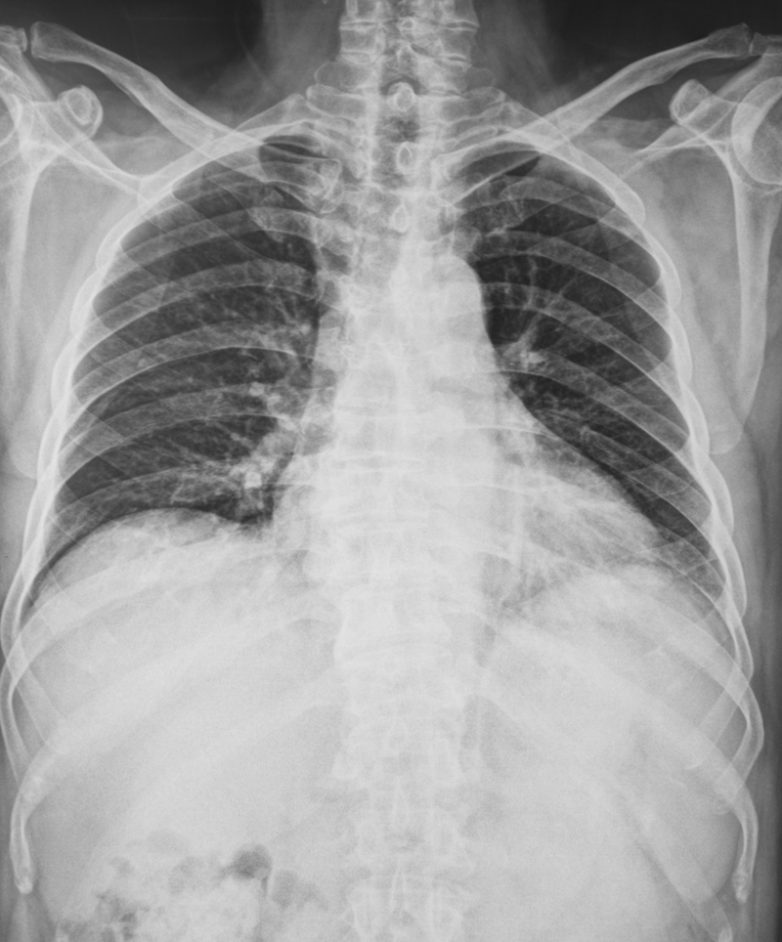

Рентген легких и ЭКГ.Эхо-кардиограмма (УЗИ сердца) для обследования структуры сердца.Чреспищеводная эхокардиография (детальное исследование структуры сердца на наличие внутрисердечных тромбов).Коронарография.Биохимические анализы крови: общий, на сывороточный креатинин, на гормоны щитовидной железы.Анализ мочи для диагностики гипертонии, вызванной почечными болезнями.